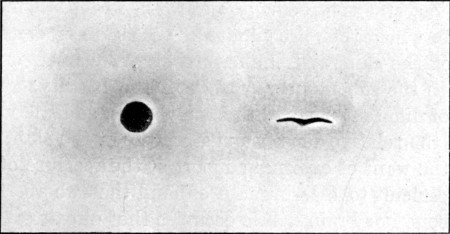

20. Circular Entry, Slit Exit Wounds59

21. Circular Entry, Starred Exit Wounds59